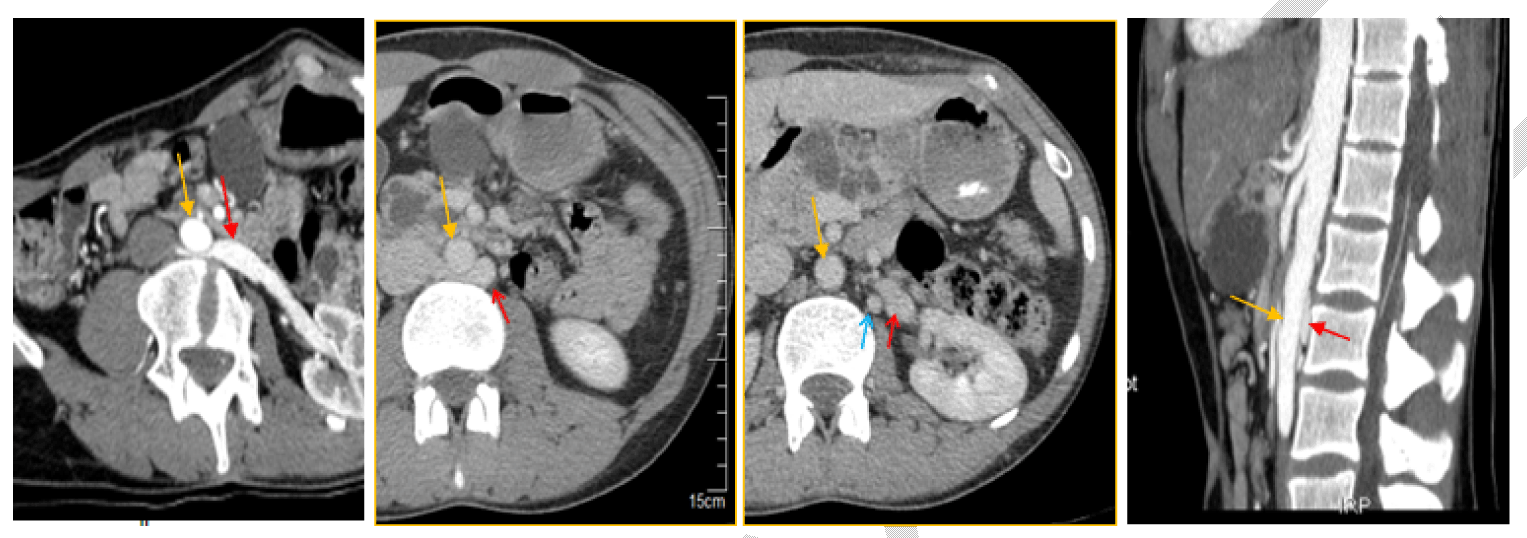

At the second step, and as an incidentally finding, the abdominal computed tomography (CT) scan done for VHL disease investigations, revealed a vascular compression: left renal vein passing posterior to the aorta, entrapped between the aorta and the vertebral column. Left gonadic vein, drained to the second left renal vein, was dilated with multiple pelvic venous collaterals. These aspects were indicative of posterior NCS (Figure 5). Interviewing the patient after discovering the vascular compression (posterior NCS), he complained of intermittent and various symptoms: urinary (intermittent macroscopic hematuria, intermittent left flank pain and chronic pelvic pain aggravated by physical activity) and systemic signs dominated by chronic fatigue and persistent headache. All these symptoms lasted for his childhood; without definitive diagnosis, despite a long investigational history of several imaging examinations and laboratory tests. In addition, high degree of left varicocele was noted at physical examination; laboratory tests revealed anemia at 10.0 mg/dl, microscopic hematuria, and 24 hour urine collection analysis showed elevated proteinuria.

Figure 5: Computed tomography showing compression of the left renal vein (red arrow) between abdominal aorta (yellow arrow) and vertebral column with dilatation of the spermatic vein (blue arrow).